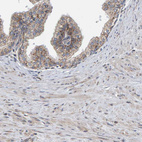

Immunohistochemical staining of human kidney, liver, prostate and small intestine using Anti-MRPL45 antibody HPA023385 (A) shows similar protein distribution across tissues to independent antibody HPA023373 (B).